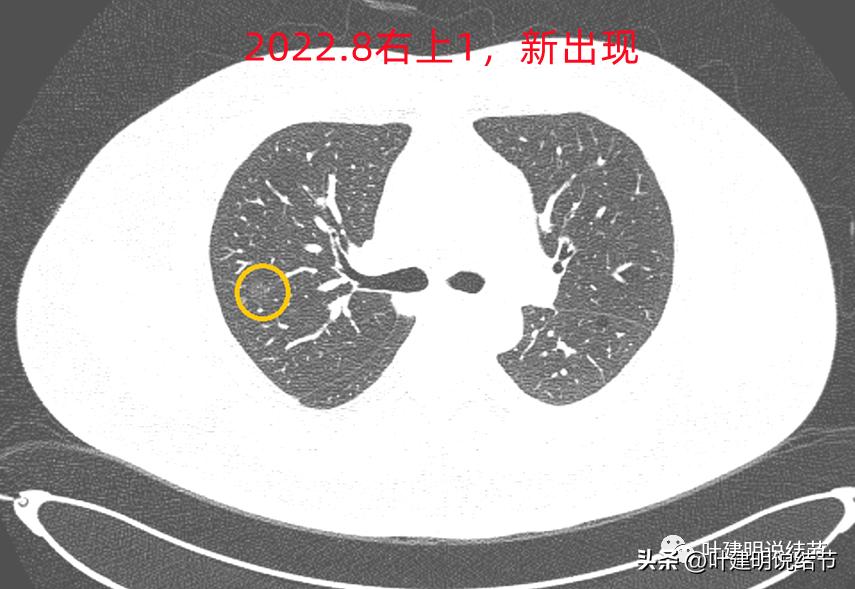

右上叶倒又出现了新的病灶:

右上病灶1:是新出现的,密度甚低,但轮廓较清,不典型增生吗?

2020年时同样位置是没有异常的:

还敢判定右上的病灶是恶性范围的不典型增生或原位癌吗?我是连左上病灶4都不敢了!还好,我觉得我们不必去纠结这几个病灶到底是不是肺癌或腺体前驱病变,反正至少风险很低,能随访就是了,肯定不能建议手术或消融等干预,也不需要穿刺活检。只要仍继续随访,半年吧!将结果交给时间来判断。